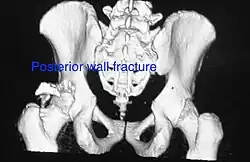

Posterior wall fracture as seen on 3-D CT scan -

Posterior column and wall fracture as seen on 3D CT -